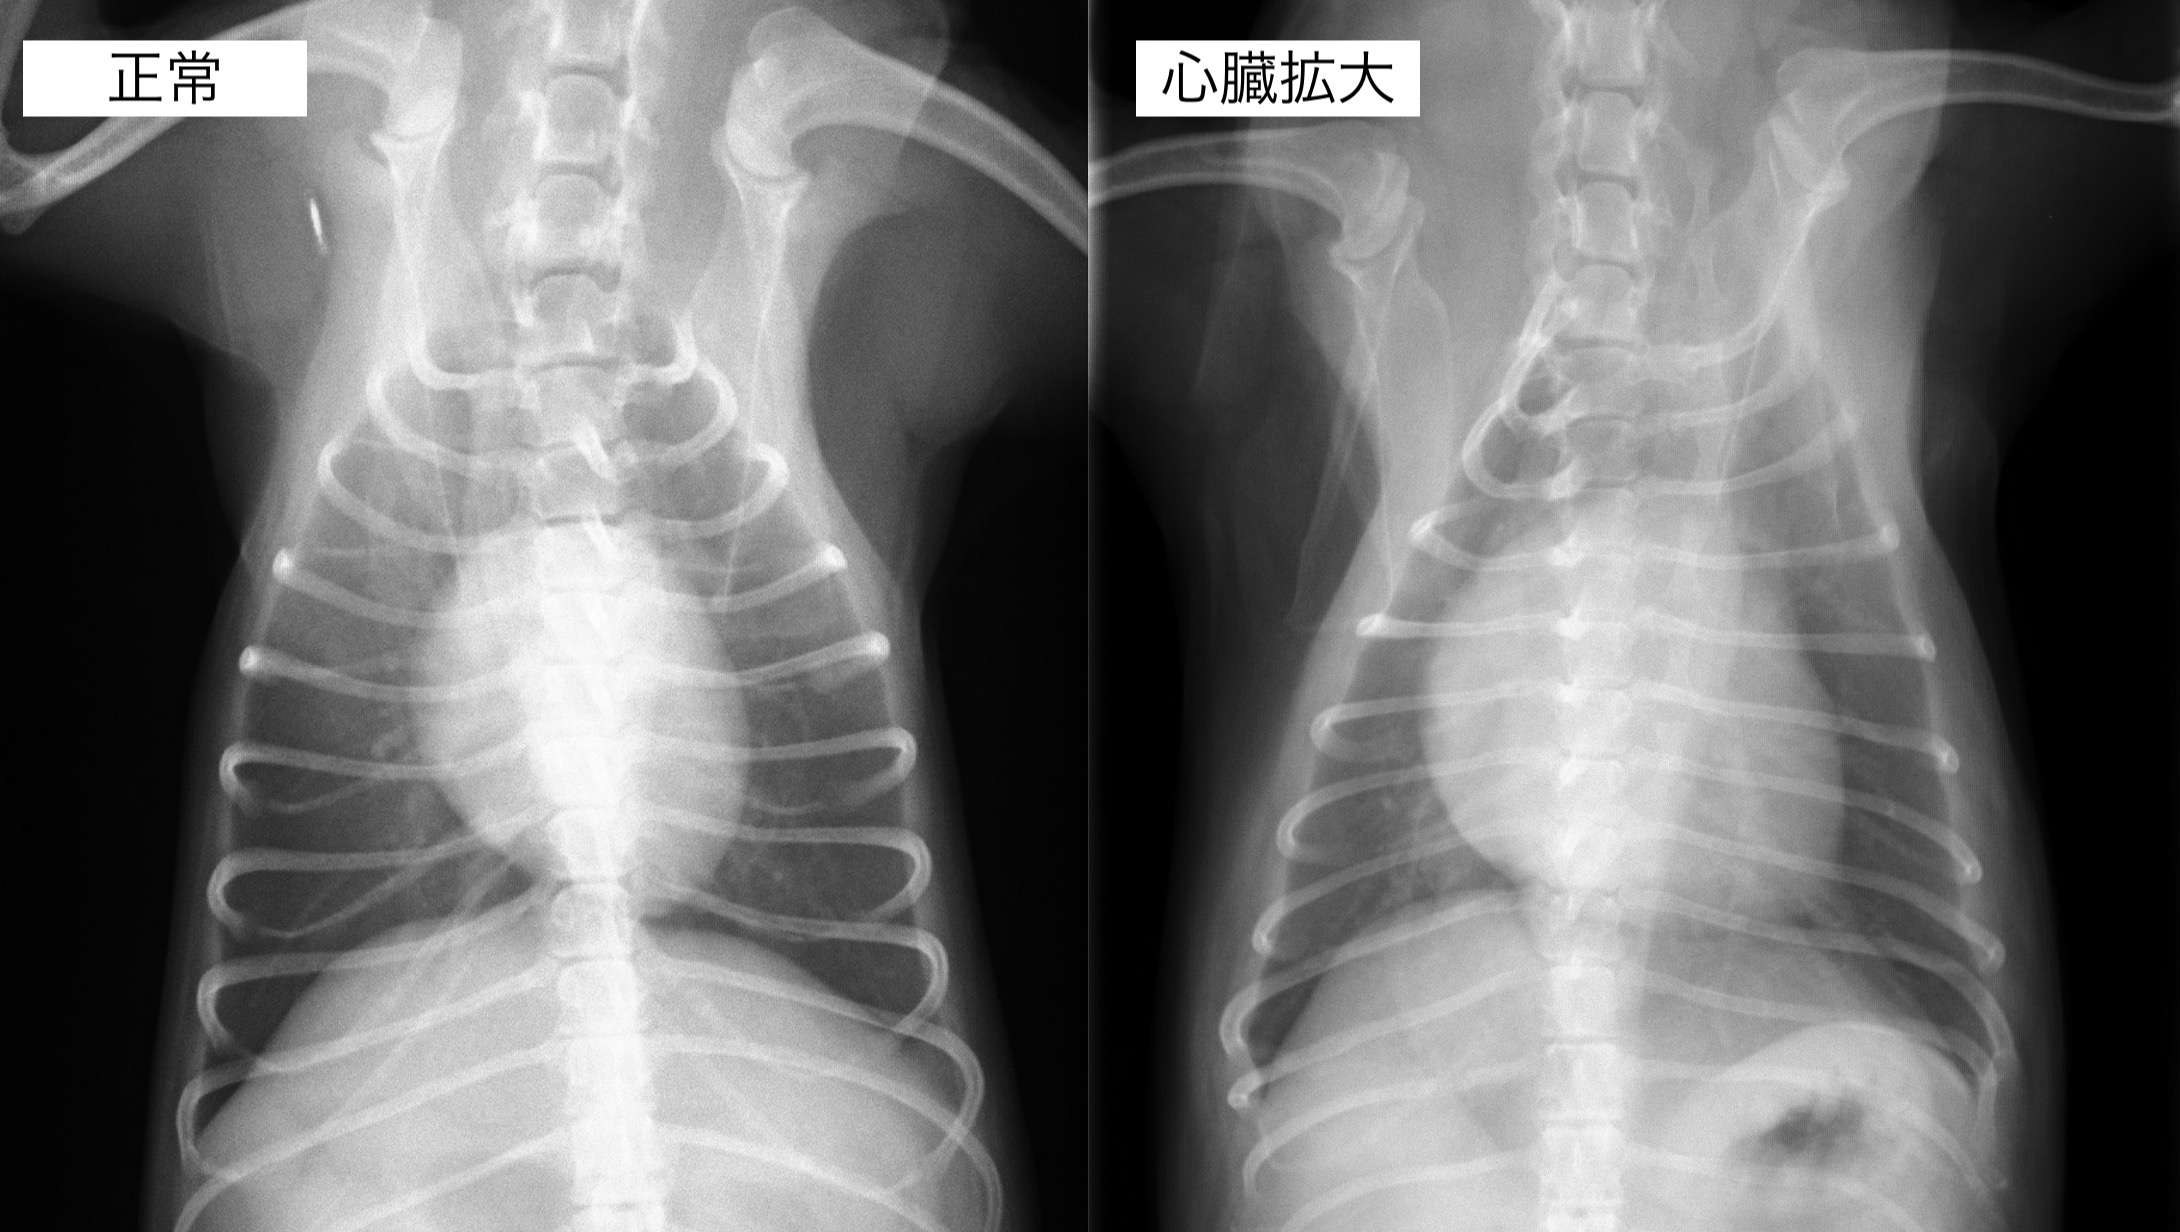

聴診検査にて心雑音が観察され、レントゲンん検査では心臓の明らかな拡大が認められました。